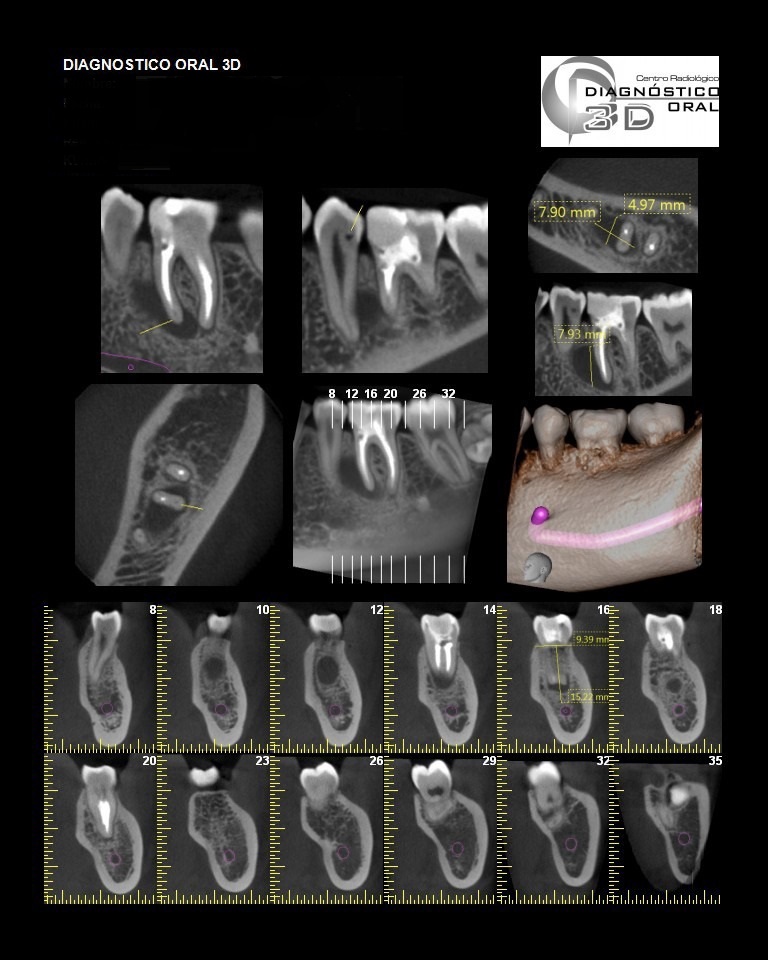

El Centro Radiológico Diagnóstico Oral 3D, es una empresa antioqueña que ofrece a sus pacientes desde el año 2009, tecnología de vanguardia en radiografías tridimensionales con calidad fotográfica. Las posibilidades para mejorar la eficacia en los diagnósticos bucales son evidentes, también lo son las posibilidades de manipulación de imagen. El sistema de imágenes en 3D ofrece detalles sin precedentes, convirtiéndola en la opción idónea para la mayoría de aplicaciones odontológicas, incluyendo implantes, tratamiento de conductos, ortodoncia, odontopediatría, periodoncia y cirugía

El mayor beneficiado con el uso de esta tecnología es el paciente, el cual podrá ser evaluado en todas sus dimensiones con una baja dosis de radiación, con un costo accesible y sin contaminar  el medio ambiente. Dependiendo de la necesidad del paciente, hay varios tipos de tomografías y los especialistas en el área odontológica hacen uso de ellas según su especialidad.

La radiología oral especializada es fundamental para una práctica dental integral, proporcionando información específica que influye en la toma de decisiones clínicas y mejora los resultados del tratamiento para los pacientes